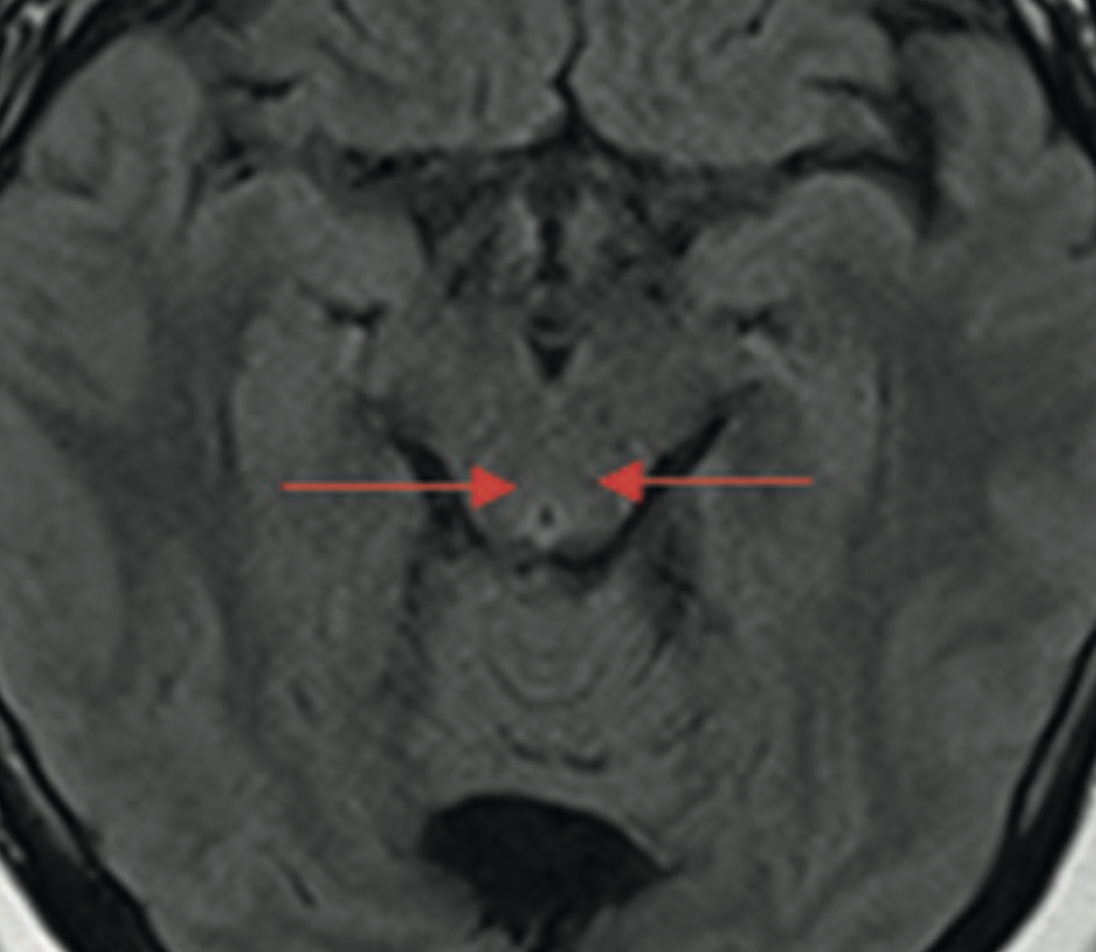

Owen Korn Bruzzone, Paula Leon Acuña, Paula Csendes González

|

|